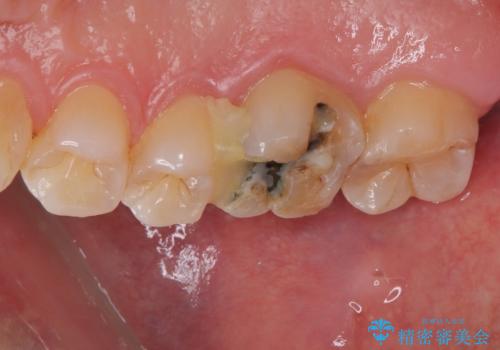

- メンテナンスで通っていただいている患者様で、銀歯が外れたので診てほしいとのことで来院された患者様です。以前にも何度か同部位が外れる度につけ直している状況でした。又、遠心口蓋側咬頭がかけている状態でなるべく歯を削らずセラミックの詰め物を入れたいとのことでハイブリッドアンレーで治療していくことになりました。

拡大鏡視野下で虫歯、古いプラスチック(コンポジットレジン)を除去し、ハイブリッドアンレーに適した形に整えました。